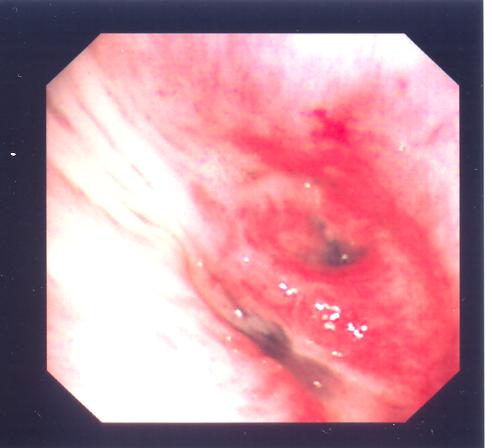

Flexible bronchoscopy on 28 Jan 2010 showed her LB6 was obstructed by a cystic mass ( fig.1) . Bronchial aspirate was negative for acid fast bacilli and malignancy. Biopsy was not taken because of the suspicion of carcinoid tumour.

Fig. 1 (Above) Patient 1 with LB6 obstructed by a mass